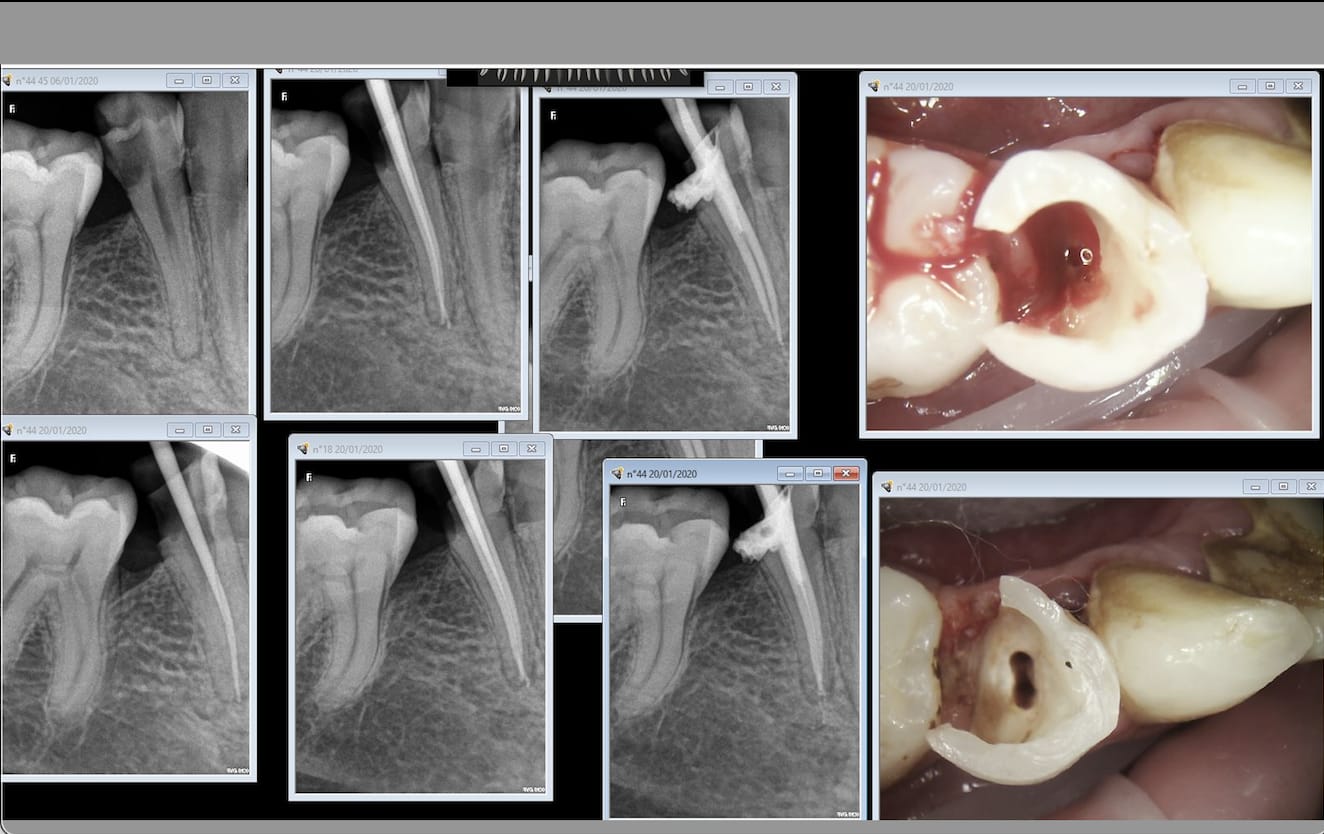

Ce matin reprise de traitement de 16 pour un ami qui habite la Suisse.

Un lentulo cassé dans la racine palatine, obturation sur 4 mm sur la mp et rien sur la dp.

C'était la rte en France ou extraction implant en suisse.

Et surtout formes toi auprès de ceux qui savent faire et qui nen font beaucoup avec des résultats reproductibles. En une semaine je dois faire les endos que fait un prof en 6 mois. -)

Pugilat mis à part, la difficulté de l'endo est surévaluée. A vu de nez, 90% se gèrent sans soucis si on bosse consciencieusement et bien équipé. Quand je vois une endo à mi racine et un canal d'un mm de diamètre qui continue jusqu'à l'apex sur une pano, pas besoin d'avoir vu 600 traitements pour faire mieux.

Reste 5% d'endos merdiques prévisibles à adresser, et 5% imprévisibles qu'il faudra identifier le plus tôt possible avant d'avoir fait une perfo ou pété une lime.

Tu le dis toi même, un bon praticien a des résultats reproductibles, et c'est pour moi plus une question de technique que d'expérience, même si cette dernière aide évidemment à acquérir la première.

Les endos pourris que je vois passer, c'est avant tout le résultat de praticiens qui s'en foutent.

Je n'ai pas dit facile, j'ai dit gérable en bossant consciencieusement avec du bon matos dans la majorité des cas. Quand on dit endo, on pense tous endo molaire qui fait suer, mais on oublie qu'au final il y a au moins autant d'endos sur des monoradiculées.

Bon, chapeau pour la 2ème qui a une séparation des canaux assez basse qui a du être assez pénible à préparer et la négociation de la courbure de la 4ème. Les autres ont 2 canaux mais l'accès semblait relativement aisé et leur naissance assez haute pour qu'on ne puisse pas vraiment les rater.

Et très sérieusement et je pose la question car je me la pose vraiment, pour chacune de ces dents, est-ce que tu considères qu'elles ont été difficiles à traiter?

J'entends par là avec un risque d'échec (casse, oubli de canal, obturation incomplète, ...) élevé qu'un praticien lambda consciencieux qui aurait pris le temps nécessaire n'aurait pas sur gérer, et que toi tu as su gérer uniquement grâce à ton expérience (et tes formations peut être?) ?